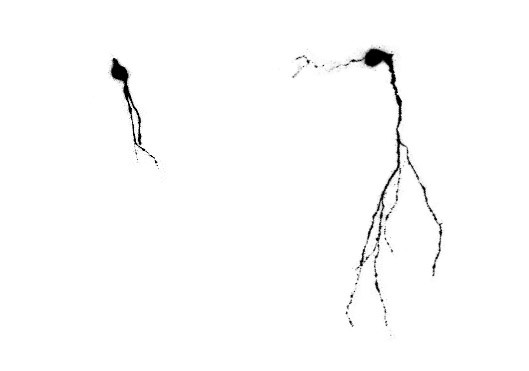

Animales envejecidos sedentarios presentan neuronas con cables muy cortos (izquierda), mientras que si realizaron ejercicio o tuvieron estímulos cognitivos las neuronas están muy desarrolladas y conectadas al circuito cerebral (derecha). (Foto: Agencia CyTA-Fundación Leloir)

“Estas neuronas sin el ambiente enriquecido tienen cables cortos e inmaduros, incapaces de recibir o mandar información”, comenta Trinchero. “Sin embargo, al exponer los animales a un ambiente lleno de estímulos, los cables de estas neuronas crecen rápidamente, pareciéndose más a neuronas de animales jóvenes. Las neuronas nuevas pasan a incorporarse eficientemente al circuito del hipocampo”.